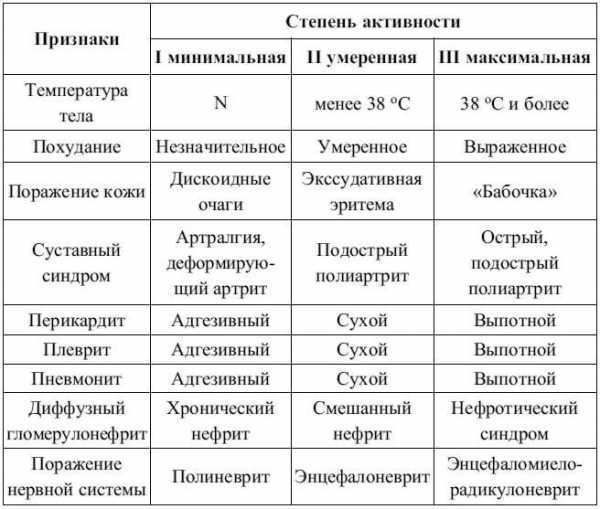

Классификация системной красной волчанки

По развитию заболевания:

- Острое начало. На фоне полного здоровья резко появляются волчаночные симптомы.

- Субклиническое начало. Симптомы появляются постепенно, и могут симулировать собой другое ревматическое заболевание.

Течение заболевания:

- Острое. Обычно больные могут с точностью до нескольких часов сказать, когда у них появились первые симптомы: поднялась температура, появилось типичное покраснение кожи лица («бабочка»), заболели суставы. Без правильного лечения уже через 6 месяцев поражаются нервная система и почки.

- Подострое. Самый частый вариант течения волчанки. Заболевание начинается неспецифично, начинают болеть суставы, ухудшается общее состояние, могут появляться высыпания на коже. Болезнь протекает циклично, с каждым рецидивом вовлекая в процесс новые органы.

- Хроническое. Волчанка длительное время проявляется рецидивами только тех симптомов и синдромов, с которых она началась (полиартрит, кожный синдром, синдром Рейно), не вовлекая в процесс другие органы и системы. Хроническое течение заболевания имеет самые благоприятные прогнозы.

Классификация по стадиям

СКВ имеет широкий спектр симптомов. Во время болезни происходят обострения и ремиссии.

Волчанку классифицируют по формам её течения:

- Острая стадия. У самой злокачественной формы наблюдаются непрерывно-прогрессирующее течение, резкое нарастание, многочисленные проявления и устойчивость к терапии. Такой тип обычно характерен для детей.

- Подострая. Обострения происходят периодично, симптомы выражены меньше, чем при острой форме. Работа органов нарушается в течение первых 12 месяцев волчанки.

- Хроническая. Один или несколько первых признаков болезни характеризуются долговременным проявлением и благоприятными прогнозами.

Также выделяют стадии заболевания. Минимальная характеризуется слабыми головными и суставными болями, высокой температурой, недомоганиями и первыми проявлениями волчанки на коже.

При умеренной фазе сильно поражаются лицо и тело, а затем — сосуды, суставы и внутренние органы. На выраженной стадии нарушена работа различных систем организма.

Симптомы заболевания зависят от стадий развития патологического процесса.